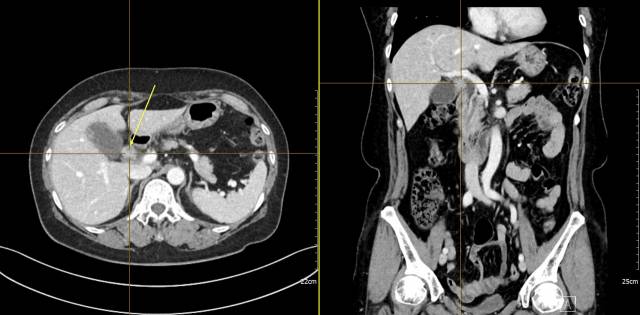

이처럼 진단 자체가 늦어지다 보니 수술적으로 완치가 쉽지 않다. 대다수 환자가 고식적 항암치료를 받는데 항암치료를 받더라도 전이성 담낭암 환자의 생존기간(중간값)은 11~12개월에 불과하다. 병원에서는 원인 불명의 복통이나 황달 등의 증상이 지속되면 초음파 검사나 전산화단층촬영(CT)을 통해 담낭 벽을 촬영한다. 이 때 담낭 벽의 비후나 혹을 발견하면 담낭암을 의심할 수 있다. 전이가 없는 경우 수술을 통해 담낭을 절제하고 조직검사를 통해 담낭암을 최종 진단하게 된다. 그에 반해 원발 담낭암과 함께 전이 소견을 보인다면 담낭보다 조직검사가 좀 더 편한 부위의 조직을 확보해 조직검사를 시행하고 전이성 담낭암을 진단할 수 있다.